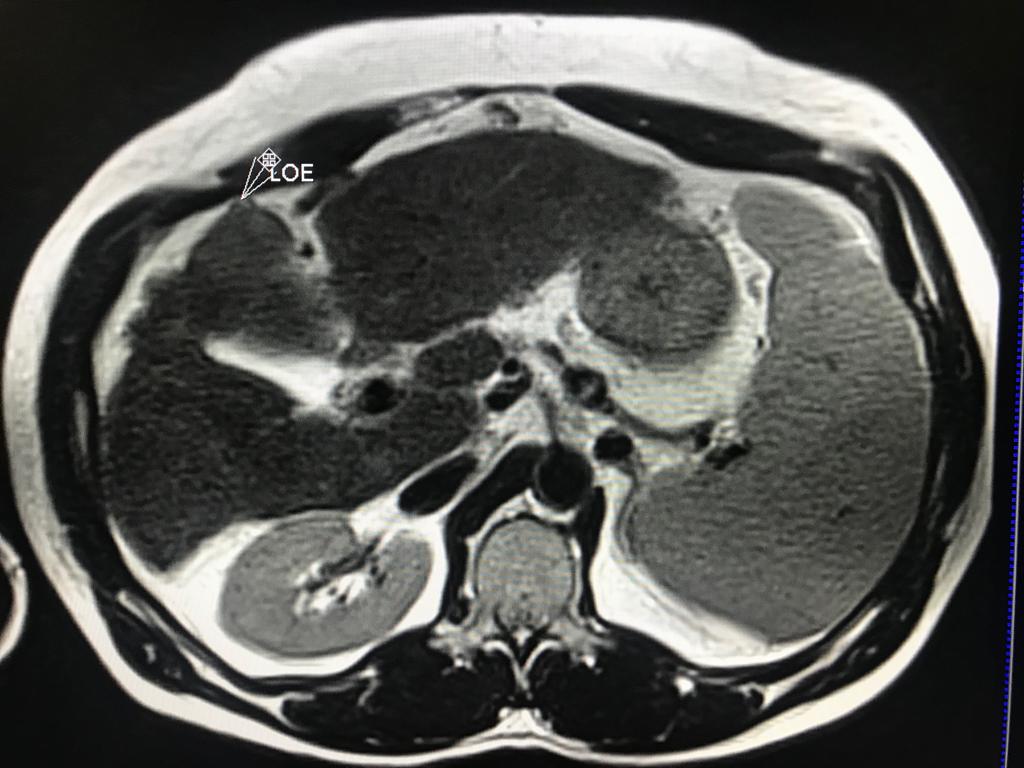

En este contexto, toda nodulación mayor de 1 cm, debe ser evaluada idealmente con RM trifásica con secuencia de Difusión , para discriminar si se trata de nódulos de regeneración , nódulos displásicos o hepatocarcinoma.

En el presente caso, encontramos una lesión típica de hepatocarcinoma en el segmento 5 ( hiperintensa en T2, restringe en la Difusión con ADC bajo. Realza heterogéneamente postcontraste EV, con wash out y presencia cápsula tardía).

El objetivo es identificar dentro de la multifocalidad de nódulos , un hepatocarcinoma precoz o de pequeño tamaño , cuando la posibilidad de tratamiento con intención curativa es viable , a pesar de la cirrosis.